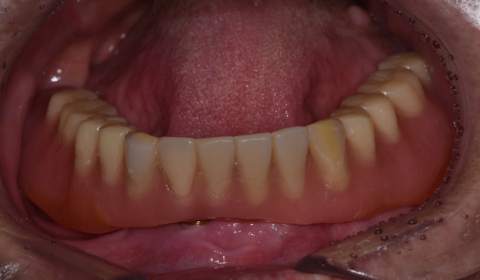

하악 부분 틀니 및 상악 전체 틀니 제작 후

따라서 아래쪽 앞니 쪽에 틀니를 잡아줄 수 있는 임플란트 두 개를 식립하여 두 개의 임플란트들을 연결하여 아래 앞니 6개를 만들어 드린 후, 어금니쪽은 부분 틀니로 보강하는 치료 방법을 선택하였습니다. 위쪽은 전체 틀니를 만들어 드렸습니다.

임플란트를 이용하여 부분적으로 치아를 만들고, 이 치아에 일정 부분의 힘을 지탱시키는 형식의 부분틀니는 전체 틀니에 비해 씹는 힘에 잘 버티고 혀나 볼의 움직임에 틀니가 탈락하지 않아 치료가 잘 마무리 되었습니다.